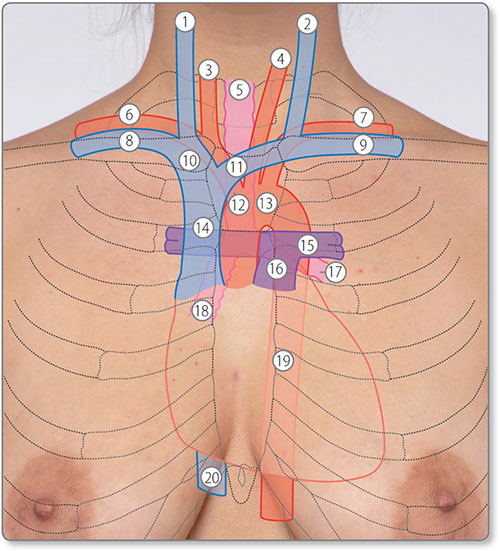

Surface anatomy and relations

The heart is in the middle mediastinum with its apex pointing inferolaterally (Figures 1.3 and 1.4). It is posterior to the sternum, costal cartilages and left lung pleura and superior to the left diaphragm. Structures adjacent to the posterior heart 2are the thoracic vertebrae, esophagus and descending aorta (Table 1.1).

Figure 1.3: Surface anatomy of the heart and great vessels. ①, right internal jugular vein; ②, left internal jugular vein; ③, right common carotid artery; ④, left common carotid artery; ⑤, trachea; ⑥, right subclavian artery; ⑦, left subclavian artery; ⑧, right subclavian vein; ⑨, left subclavian vein; ⑩, right brachiocephalic vein; ⑪, left brachiocephalic vein; ⑫, brachiocephalic trunk; ⑬, arch of aorta; ⑭, superior vena cava; ⑮, left pulmonary artery; ⑯, pulmonary trunk; ⑰, left main bronchus; ⑱, right main bronchus; ⑲, descending aorta; ⑳, inferior vena cava.